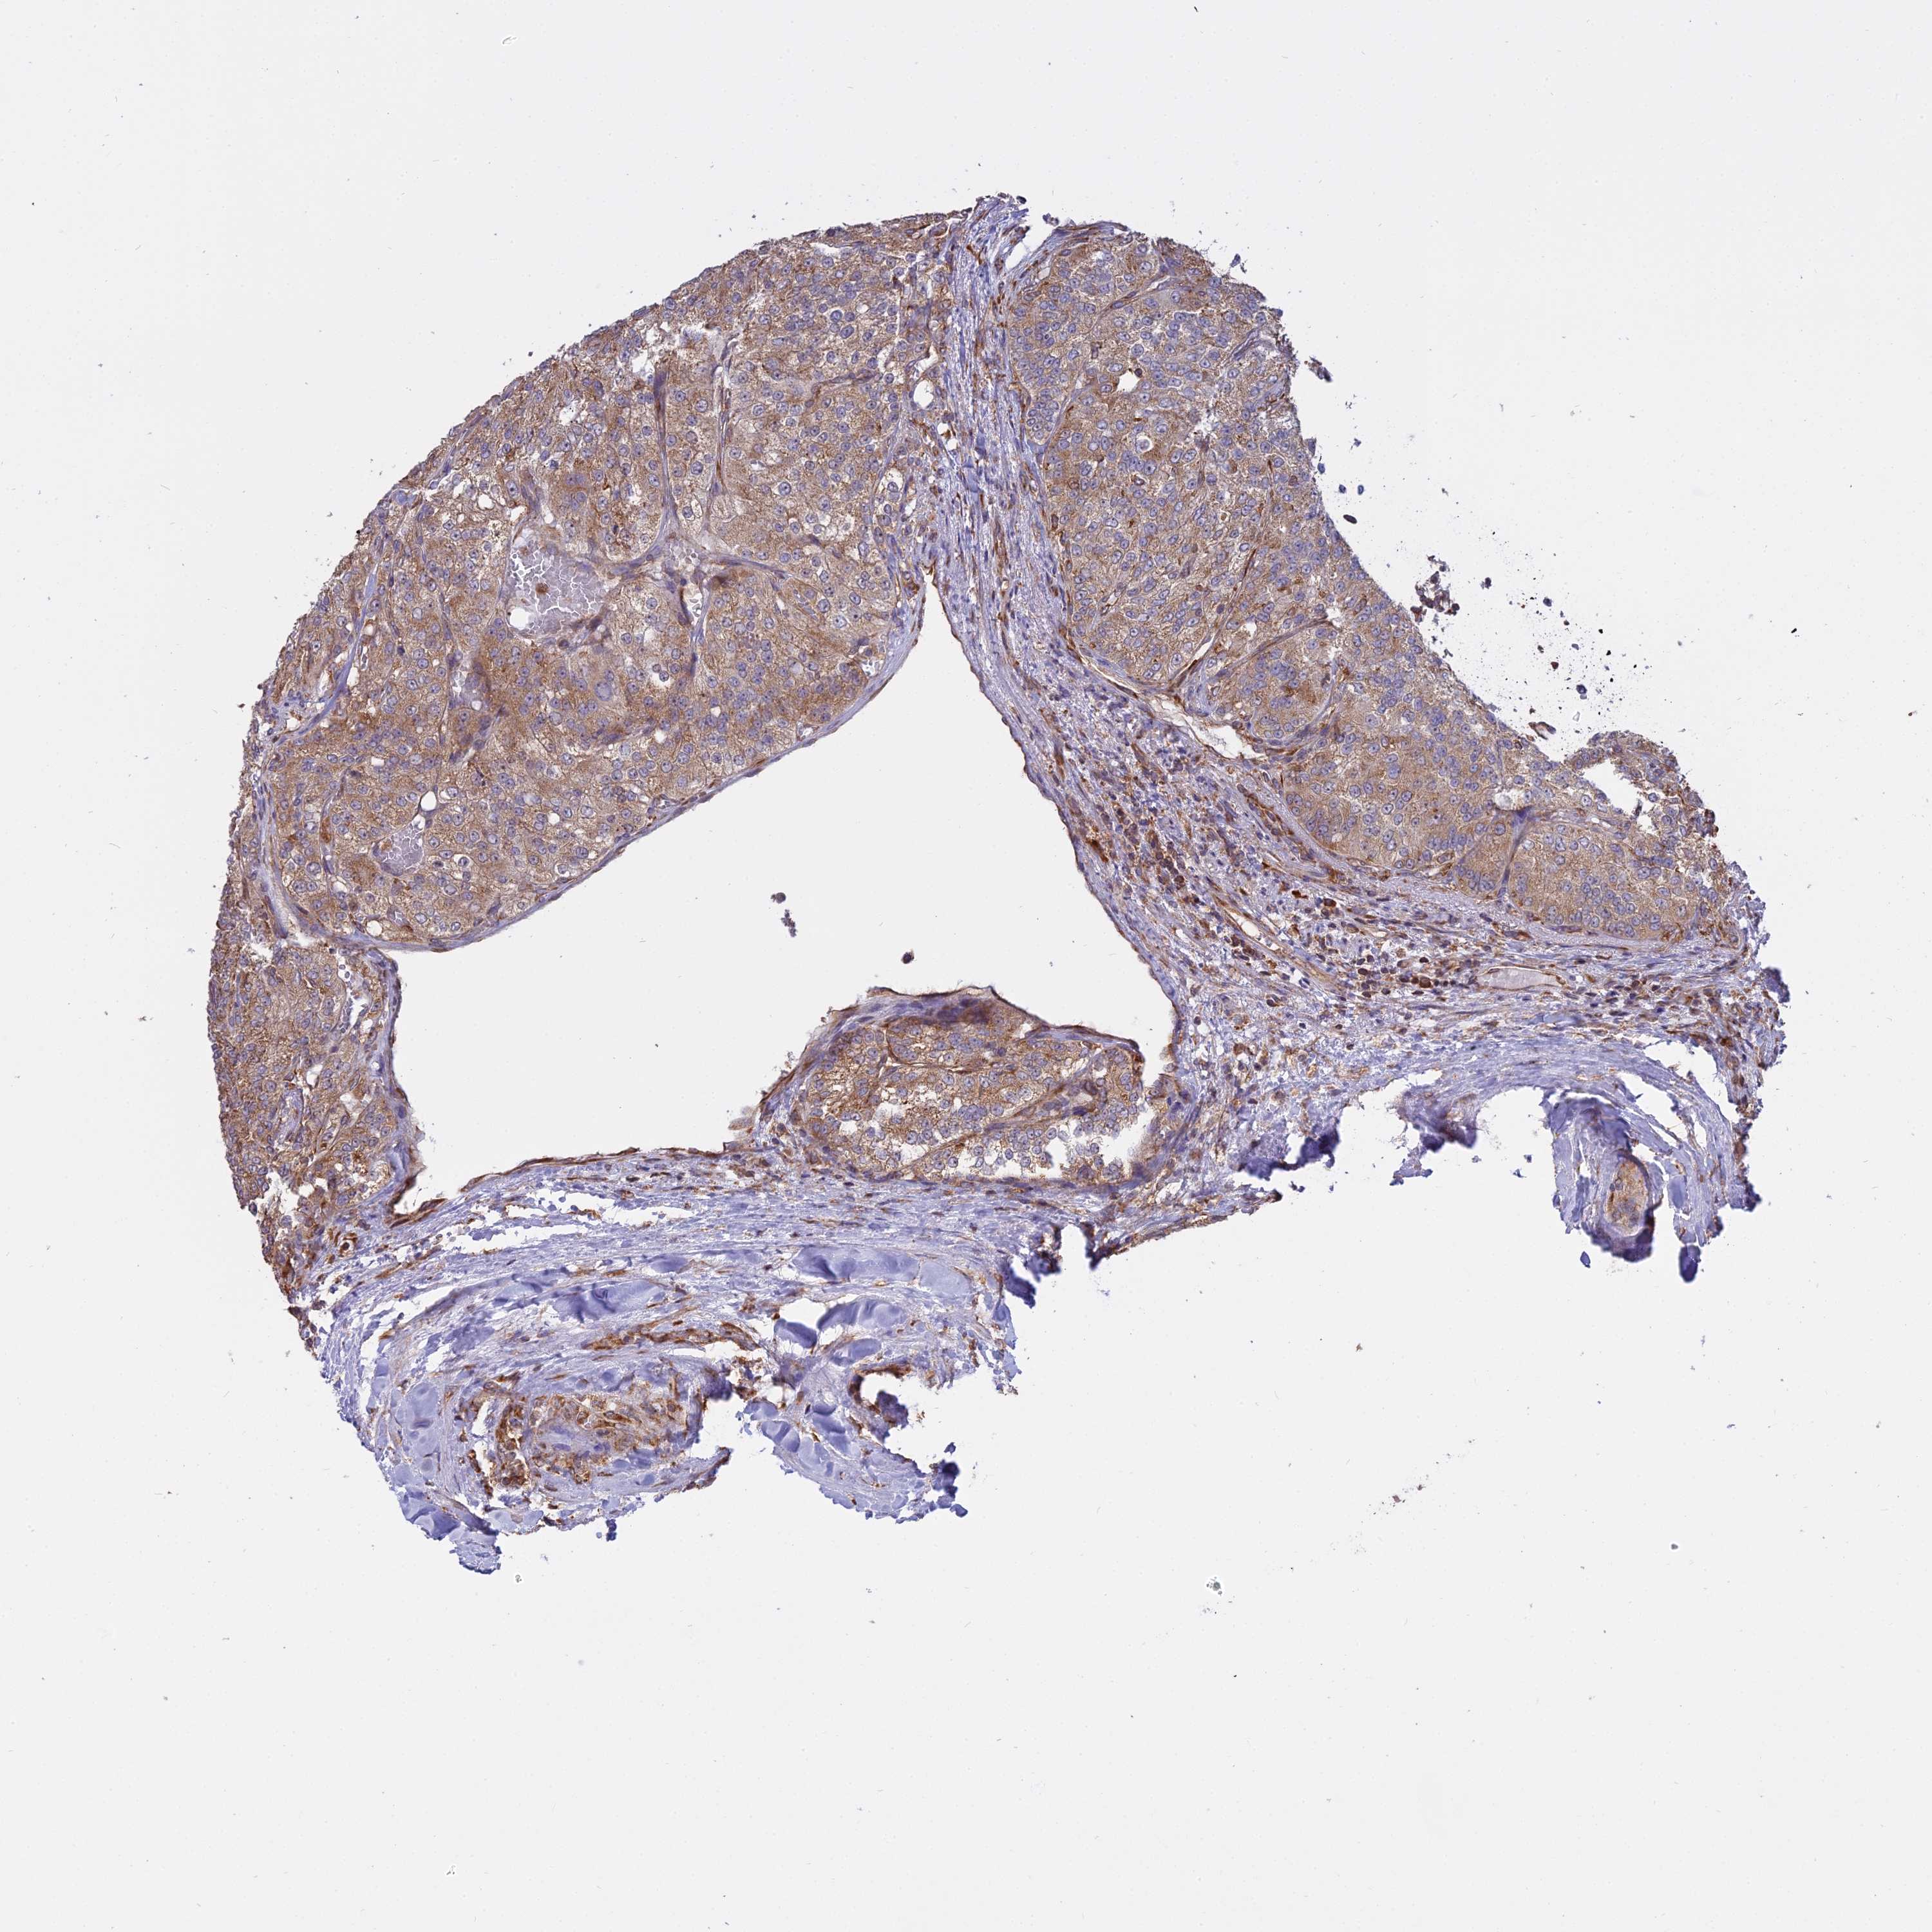

KIDNEY RENAL CLEAR CELL CARCINOMA (TCGA) - Interactive survival scatter ploti

The Survival Scatter plot shows the clinical status (i.e. dead or alive) for all individuals in the patient cohort, based on the same data that underlies the corresponding Kaplan-Meier plots. Patients that are alive at last time for follow-up are shown in blue and patients who have died during the study are shown in red.

The x-axis shows the expression levels (FPKM) of the investigated gene in the tumor tissue at the time of diagnosis. The y-axis shows the follow-up time after diagnosis (years). Both axes are complimented with kernel density curves demonstrating the data density over the axes. The top density plot shows the expression levels (FPKM) distribution among dead (red) and alive patients (blue). The right density plot shows the data density of the survived years of dead patients with high and low expression levels respectively, stratified using the cutoff indicated by the vertical dashed line through the Survival Scatter plot. This cutoff is automatically defined based on the FPKM cutoff that minimizes the p-score. The cutoff can be changed by dragging the vertical line or by entering a cutoff value in the square labeled "Current cut-off".

Under the Survival Scatter plot the p-score landscape (black curve; left axis) is shown together with dead median separation (red curve; right axis). Dead median separation is the difference in median mRNA expression between patients who have died with high and low expression, respectively. It is calculated as follows: median FPKM expression of dead patients with high expression - median FPKM expression of dead patients with low expression. This is intended to aid the user in visually exploring custom cutoffs and the associated p-scores and dead median separation.

Individual patient data is displayed and can be filtered by clicking on one or more of the category buttons on the top of the page. Categories describing expression level and patient information include: high, low, alive, dead, female, male and tumor stages. The scale of the x-axis can be toggled between linear and log-scale by clicking on the "x log" button. Mouse-over function shows TCGA ID, patient information and mRNA expression (FPKM) for each patient.

& Survival analysisi

Kaplan-Meier plots summarize results from analysis of correlation between mRNA expression level and patient survival. Patients were divided based on level of expression into one of the two groups "low" (under cut off) or "high" (over cut off). X-axis shows time for survival (years) and y-axis shows the probability of survival, where 1.0 corresponds to 100 percent.

RPL26 is potential prognostic, high expression is favorable in Kidney Renal Clear Cell Carcinoma (TCGA)

Best expression cut offi

Based on the FPKM value of each gene, patients were classified into two groups and association between prognosis (survival) and gene expression (FPKM) was examined. The best expression cut-off refers the FPKM value that yields maximal difference with regard to survival between the two groups at the lowest log-rank P-value. Best expression cut-off was selected based on survival analysis .

When clicking on this number, the vertical dashed line indicating cut-off, the interactive survival plot, and the Kaplan-Meier curve will be adjusted to show results based on the best expression cut-off.

: 1940.67

Average pTPM 2710.6

Number of samples 521